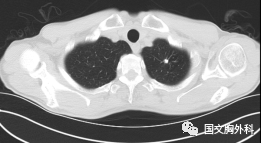

這個病人檢查胸部CT如圖3:根據(jù)影像學(xué)考慮是惡性腫瘤,行手術(shù)治療后病理回報(bào):“肺膿腫,合并炎癥纖維組織增生”,因此“肺占位”不代表就是惡性腫瘤,診斷金標(biāo)準(zhǔn)是病理診斷。如果檢查后發(fā)現(xiàn)“肺占位”先不要驚慌,及時(shí)就診請專科醫(yī)生會診指導(dǎo)治療才是關(guān)鍵。